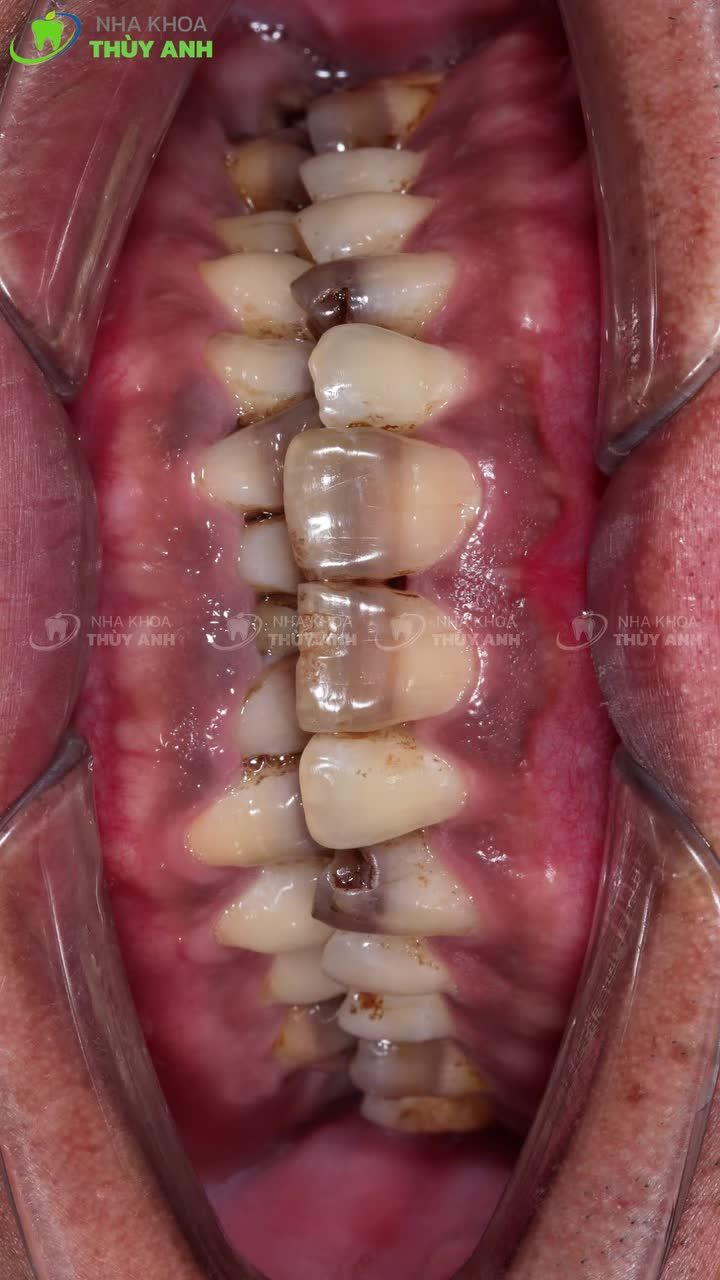

Procedures Show - Phẫu Thuật Dời Khoảng Sinh Học, Khắc Phục Răng Sứ Bị Viêm Tại Thái Nguyên